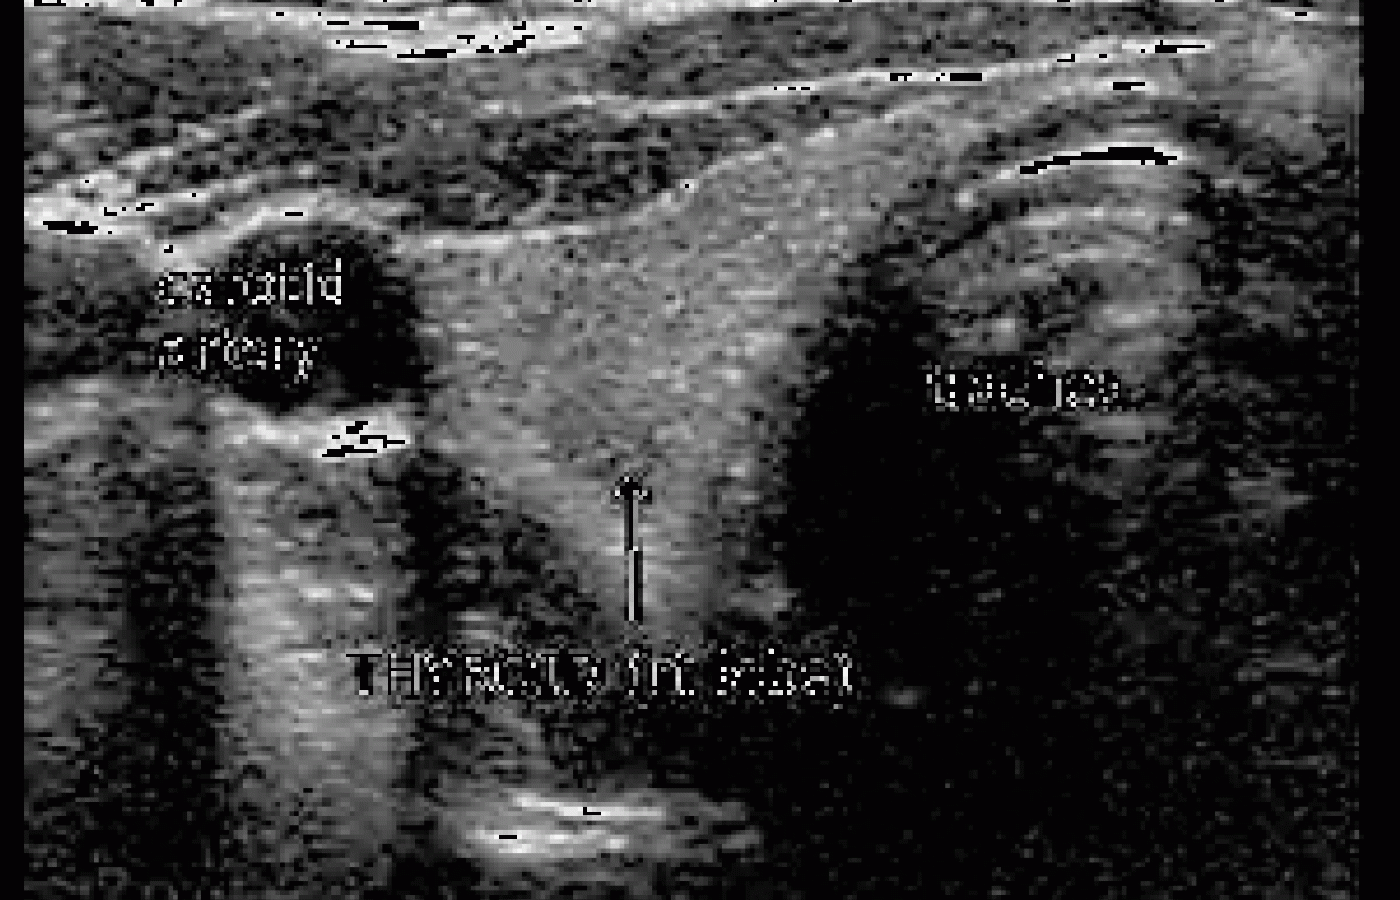

A 2-D image is constructed by "rocking" the probe from side to side, which alters the angle of the beam, giving a slightly different view of a region. At the same time, the probe is moved horizontally across the body. This is not a technique one can acquire in a few minutes; it takes some practice to obtain a diagnostic image. A significant amount of data needs to be processed to produce an image. As you can imagine, the image can change drastically, depending on the technical ability of the person manipulating the probe. Imaging technology is improving, but it still takes a skilled specialist to interpret the findings. In Figure 1, without knowing the location of this image and how it was obtained, it is just a grayscale study; what it is exactly is anyone's guess.

At this point in our discussion, it is not important to know what part of the anatomy this image represents, but suffice to say, it is not an imaging modality easily comprehended by the untrained eye. However, there are more sophisticated versions of 2-D B-scans, including real-time B-scans and 3-D imaging, which make viewing and evaluating the anatomy much easier. (see Figure 2.)